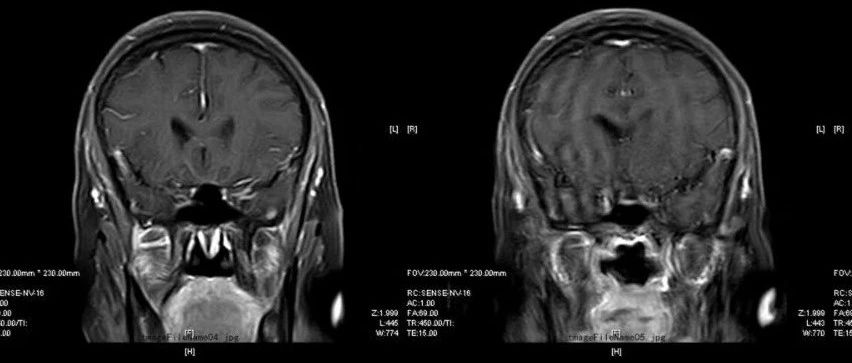

中年男性,头痛半月伴四肢乏力,请诊断!

医学影像  yxyx-app  医学影像APP,打造伴随医生快速成长的影像学习社区。与影像园(Xctmr.com)一起提供最全面的影像案例库、基础(解剖、病理、影像诊断)知识、影像技术及考题等,为医生提供最佳的医学影像参考。【所属科室】神经外科【基本资料】患者,男,59岁【主诉】头痛半月伴四肢乏力【现病史】患者半月前无明显诱因下出现头痛不适,以右枕部最明显,进行性加重,并出现恶心呕吐,为胃内容物,非喷射性,感四肢乏力,近四天无力行走。...